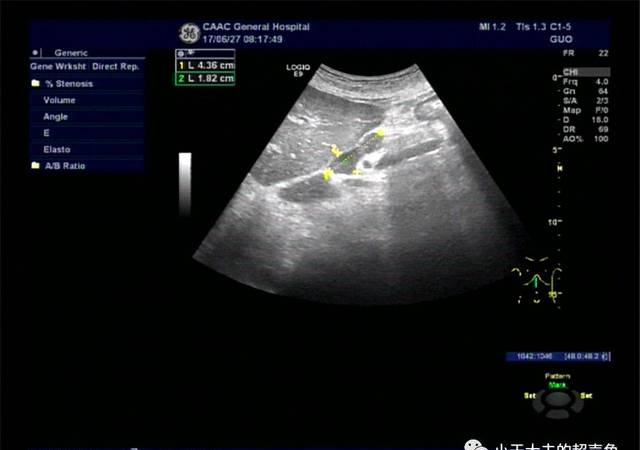

图2-1、2-2:纵切面及横切面显示胰腺旁异常肿大淋巴结,大小约4.2×1.6×1.4cm,形态欠规则,边界尚清,门样结构消失。